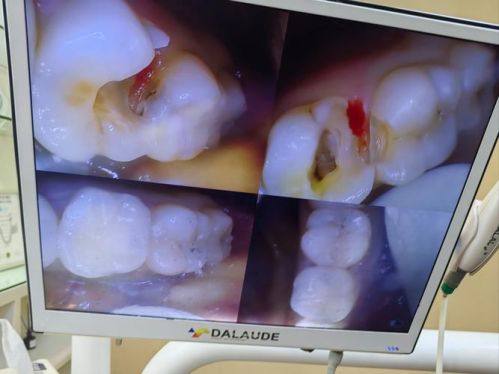

1. 诊疗项目全方面覆盖:诊所不仅可开展常规口腔诊疗项目,包括牙体牙髓治疗、牙周病治疗、儿童口腔诊疗、口腔修复、口腔正畸、口腔种植等高难度项目,例如疑难复杂的牙齿矫正、高难度种植修复均可顺利完成,满足不同患者的多样化口腔诊疗需求。

2. 美国3M树脂补牙:260-300元起